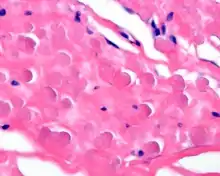

In general, the tumor is an ill defined, nonencapsulated, rubbery, and firm, white lesion with interspersed fat. The tumors can be quite large (up to 20 cm), although most are around 5 cm.[3]

By microscopie view, there is an admixture of heavy dense bands of collagenous tissue dissected by fat and abnormal elastic fibers. The elastic fibers are often quite large and are easily identified. The elastic fibers are coarse, thick, and darkly eosinophilic, often fragmented into globules, creating a "string of pearls" or "pipe cleaner" appearance. Because of degeneration, the elastic fibers will appear as globules with a serrated or "prickled" edge.[3]